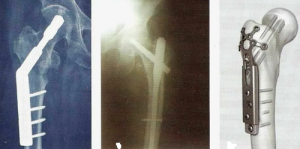

Нынешний проект рекомендаций по лечению столь частого вида переломов, однозначно ориентированы на остеосинтез, поскольку результаты его обнадеживают (рисунок 3).

Относительная сложность проведения БИОС в этих случаях, затруднение в активизации и реабилитации тучных пострадавших и риски ранней нагрузки на травмированную конечность, ведут к поискам альтернативных методов хирургического лечения вертельных переломов бедренной кости.

Ранняя активизация с возможностью полноценной нагрузки на оперированную конечность при использовании преимуществ эндопротезирования важнейший фактор благоприятного исхода лечения (рисунок 5), да и сохранения жизни этой сложной группе пострадавших.